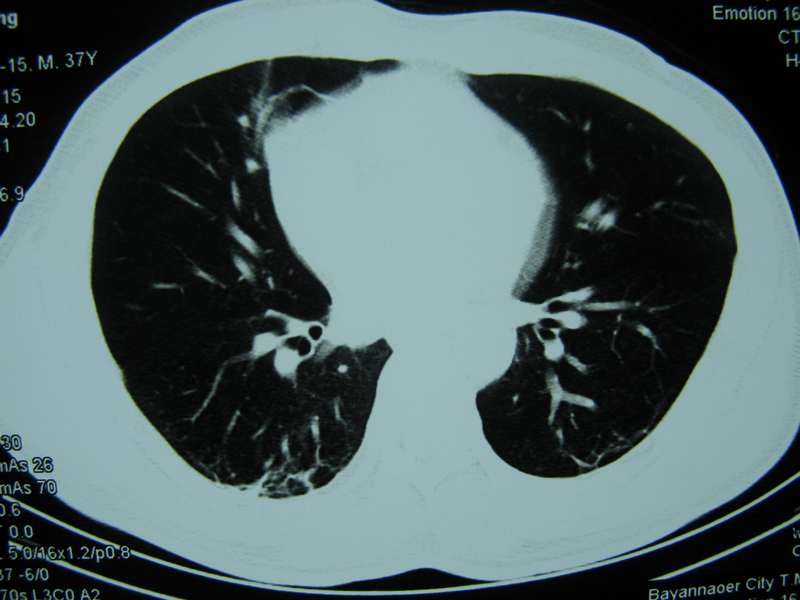

男,37岁,主述胸疼厉害,无咳嗽,无发热,血象也不高,病灶内ct值脂肪密度,右侧胸腔内少量积液,同道们考虑什么?谢谢!

脂肪垫,右下肺感染,少许积液是症状所在

纵膈脂肪堆积,右肺慢性炎症。

两肺下叶基底段纤维灶,右肺下叶基底背侧相应胸膜肥厚,右肺中叶内侧段部分不张。前中下纵隔团块状脂肪影,随访除外胸腺脂肪瘤。

脂肪垫;右肺慢性炎症。